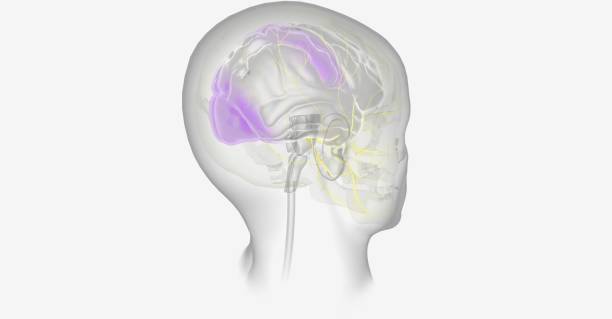

✅뇌경색 후유증 종류

뇌경색 후유증은 다양한 증상을 유발할 수 있습니다. 이러한 증상은 흔히 다음과 같이 나눌 수 있습니다.

1. 전두엽 손상

뇌경색 후, 이마 부위에 손상이 생기면 하체의 힘이 약해질 수 있습니다. 이로 인해 환자는 걷거나 움직일 때 한 쪽으로 기울거나 반쪽의 마비가 발생할 수 있습니다. 대소변의 장애, 성격 변화, 사고력 저하, 집중력 감소 등과 같은 부작용도 나타날 수 있습니다.

2. 두정엽 손상

두정엽 손상은 실인증과 관련이 있습니다. 환자는 물체를 만져보면 물체를 정확히 인식하지 못하거나, 반대편의 손으로 만졌을 때 자기 몸이 아닌 타인의 몸으로 인식할 수 있습니다.

3. 측두엽 손상

측두엽 손상은 기억력 저하, 청력 감소, 언어 기능 저하 등을 포함합니다. 이 증상은 혈관성 치매로 진행할 수 있으며, 가장 심각한 경우에는 실명에 이를 수도 있습니다.

4. 뇌관 부위 손상

뇌관은 우리 몸의 생체 징후를 담당하는 부위로, 이상이 있는 경우 음식을 적절히 소화하지 못하게 되어 식사에 어려움을 겪을 수 있습니다. 호흡 장애도 발생할 수 있어 인공호흡 장치가 필요할 수 있습니다.